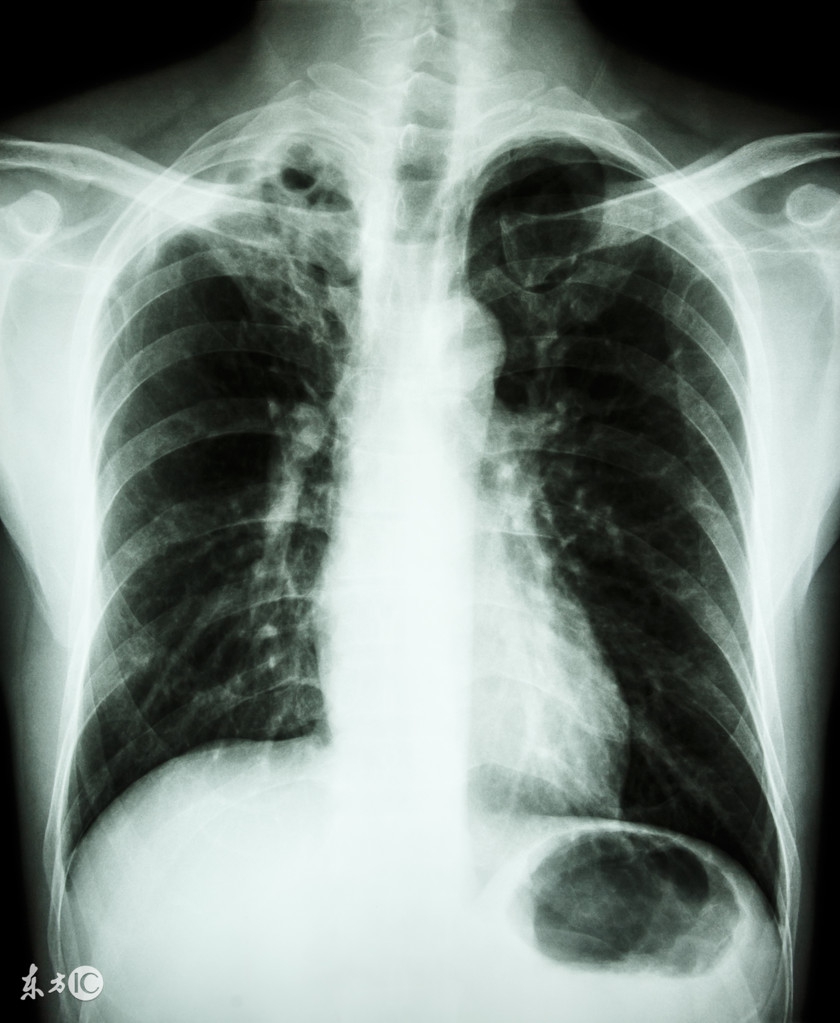

早期诊断肺结核病可以提高患者的治愈率,减少传播他人的可能性。出现以下情况应警惕本病可能:一是反复发作或迁延不愈的咳嗽、咳痰,或呼吸道感染经正规抗菌治疗3周以上仍无效;二是痰中带血或咯血;三是长期发热(常为午后低热),可伴盗汗(睡眠中出汗)、乏力、体重减轻、月经失调;四是有密切接触开放性肺结核病史等。目前我国已经对有肺结核可疑症状者实行胸透、胸片和痰涂片免费检查,对活动性肺结核患者免费提供统一方案的抗结核药物。